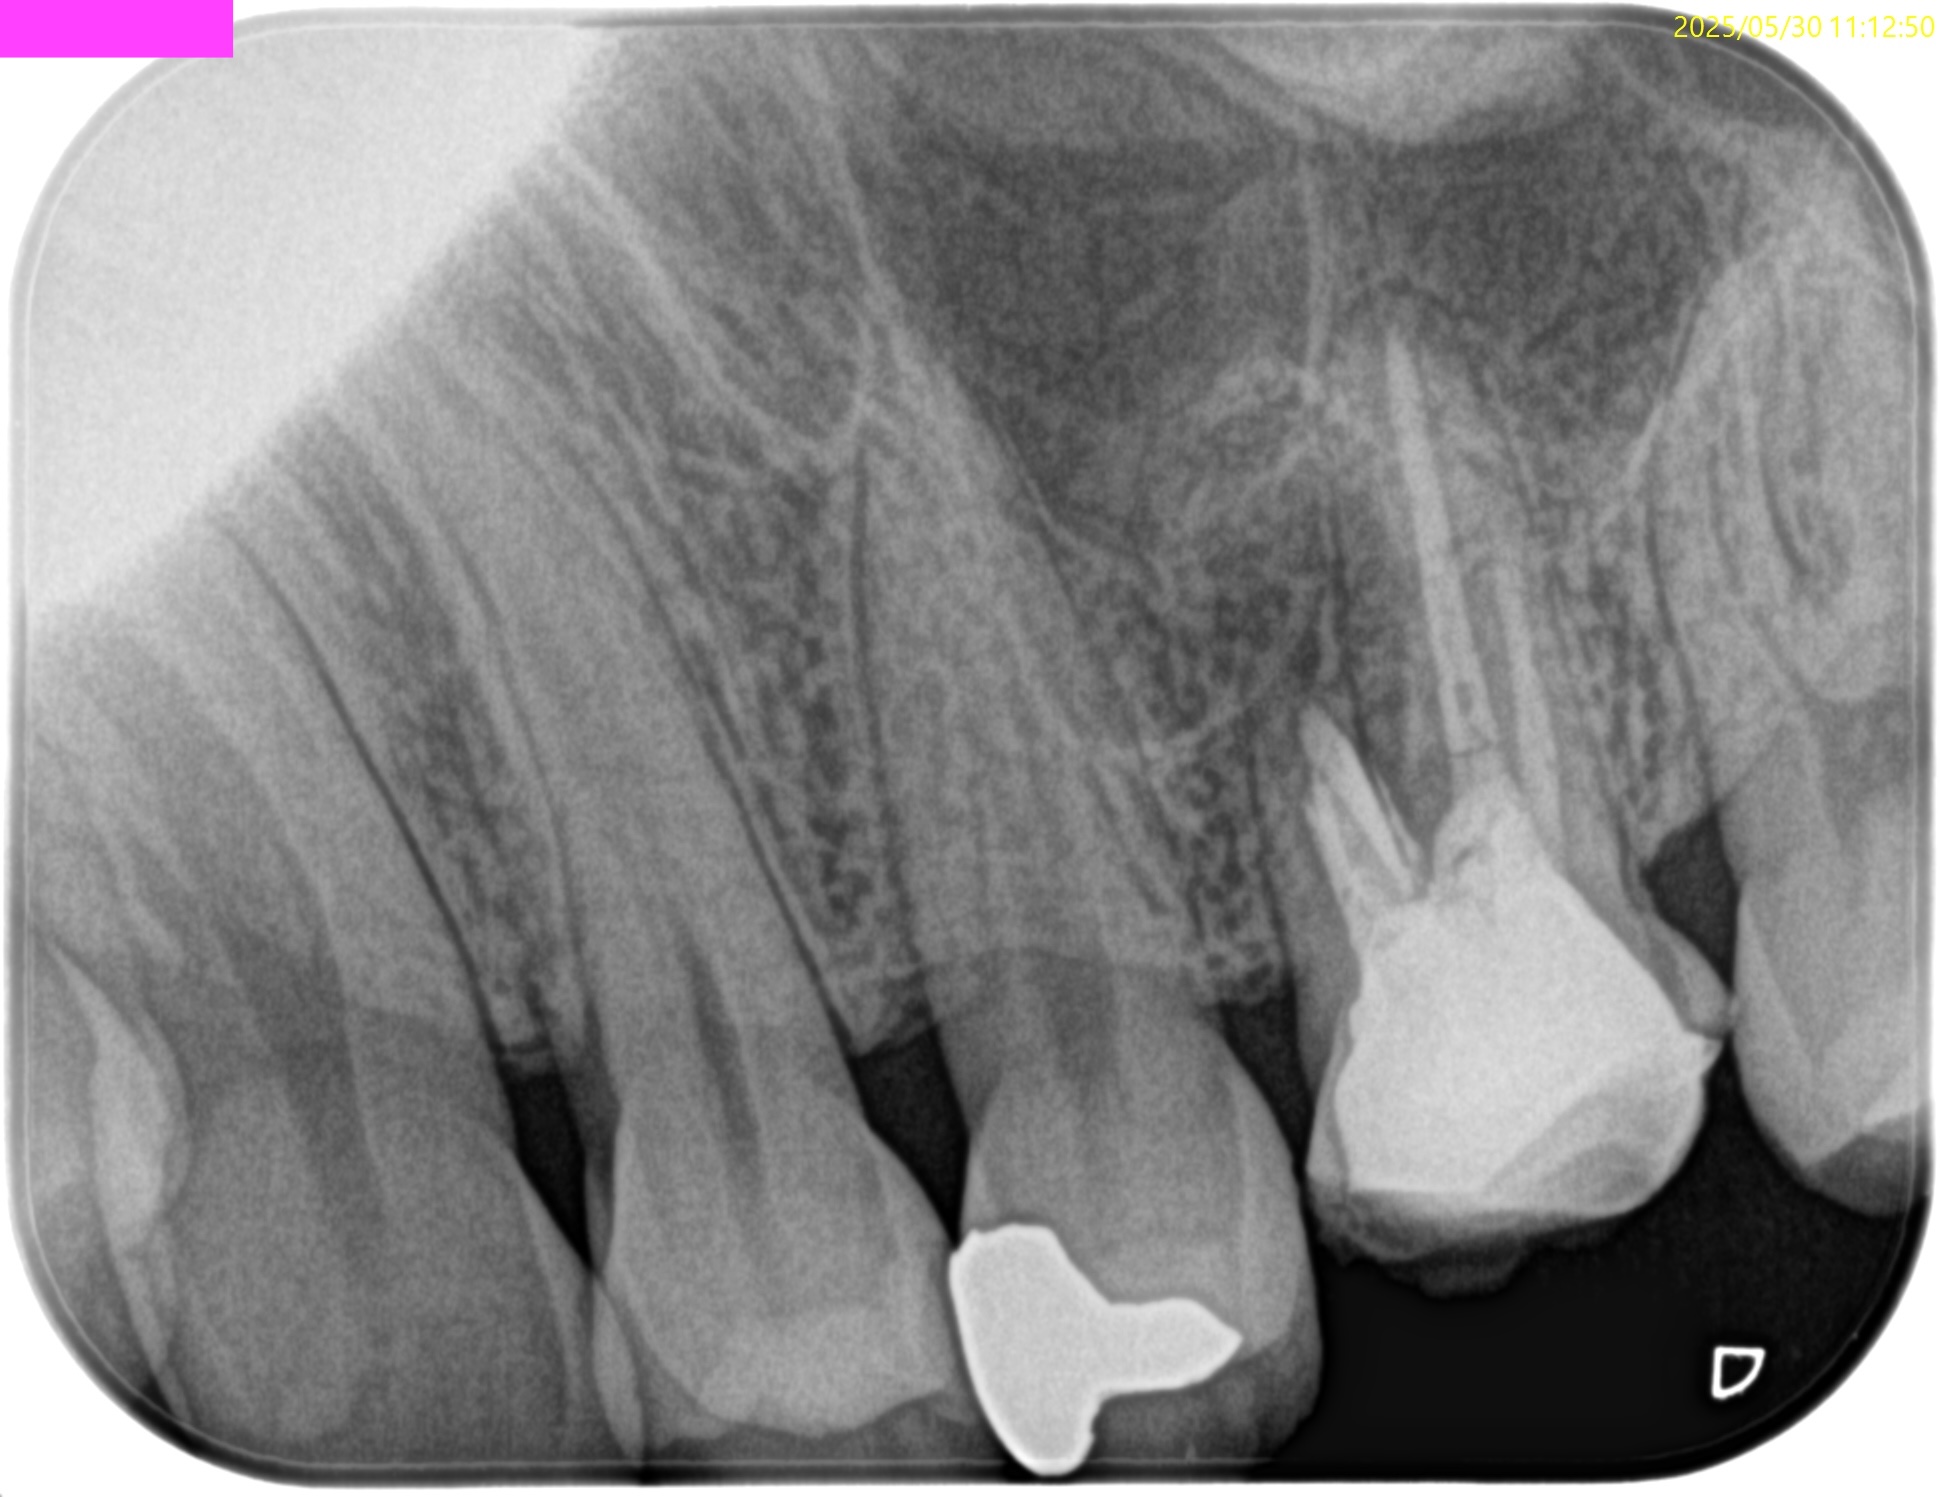

PA(2025.4.15)

MBの根管口の歯質が少ない。

垂直性歯根破折を惹起させるものだ。